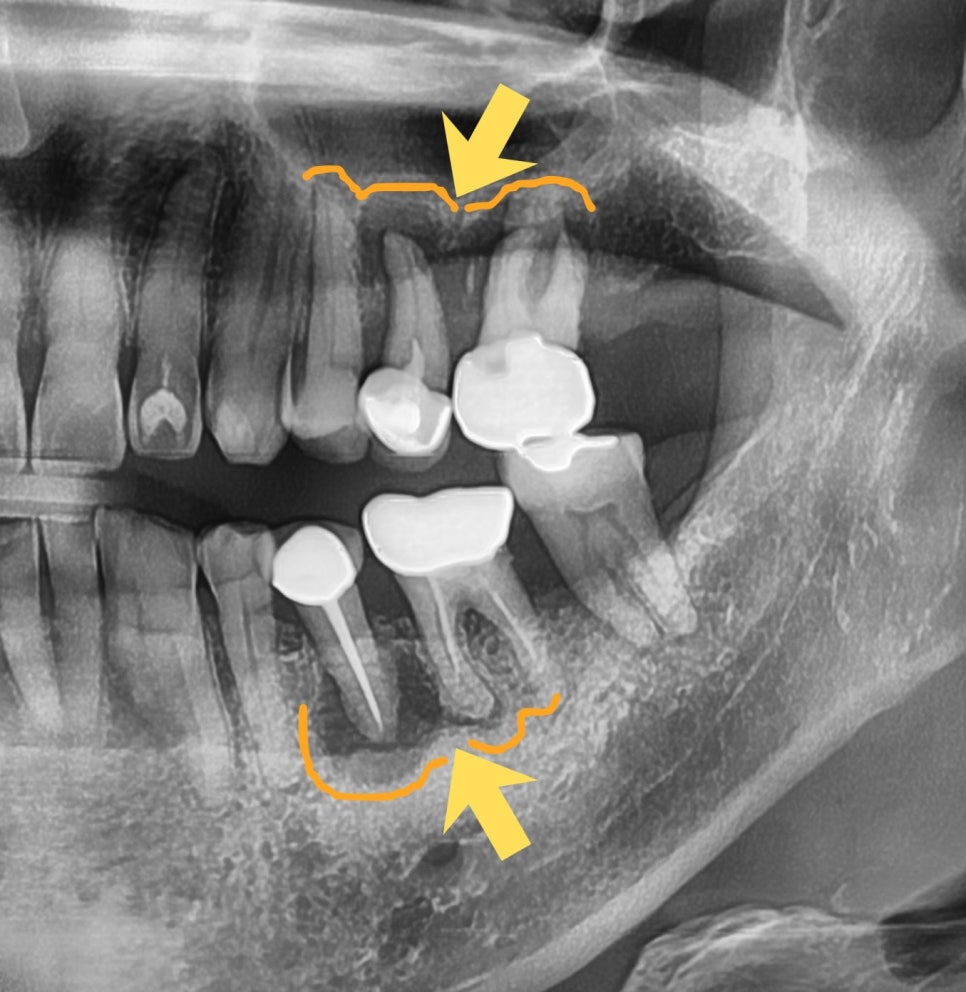

CT와 파노라마 분석 결과, 치아 뿌리 끝에 염증이 생긴 상태였고 잇몸뼈까지 녹아내리는 만성 복합치주염이 함께 진행되고 있었습니다. 남은 뼈와 잇몸을 지키기 위해 발치를 먼저 진행했습니다.

상악동 거상술 및 뼈이식

발치 후 6개월 뒤 내원 시 안쪽 뼈 상태가 좋지 않아 뼈이식과 상악동 거상술이 모두 필요한 상황이었습니다. CT 화면을 직접 보여드리며 근거를 설명드린 뒤, 위쪽을 먼저 진행했습니다.